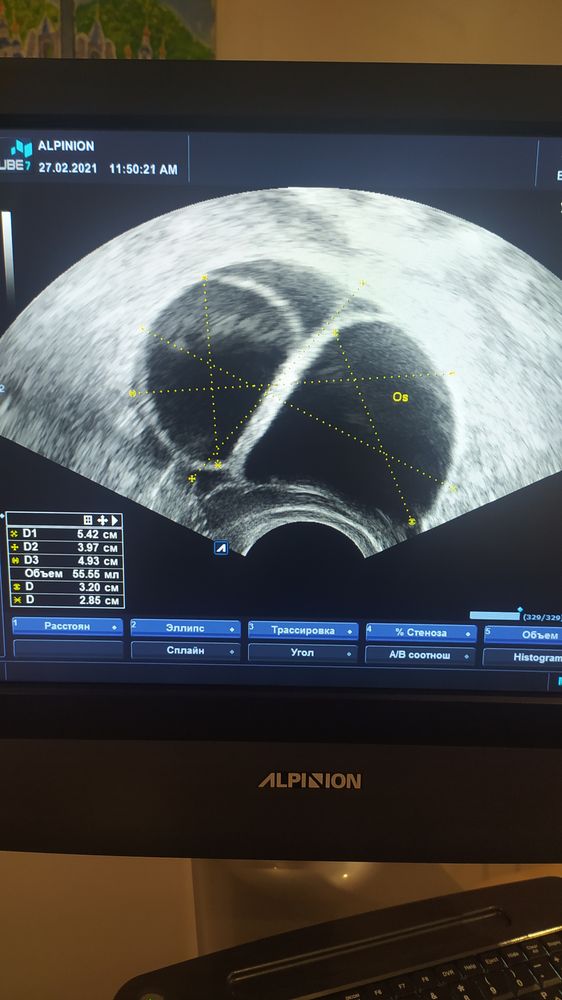

Привет девочки. Пишу и плачу... 16 ДЦ, стимуляция Летрозолом. На 12 ДЦ был укол ХГЧ 10 тысяч при размерах ДФ 20 мм и 21,5 мм. Сегодня на УЗИ ходила, чтобы подтвердить О. Итог: выросло три кисты 32,8 мм, 31,2 мм, 30 мм. УЗИ прикрепила. Почему ДФ не лопнули?! Сижу реву, настроения нет вообще. Надежды никакой. Все как и в прошлом цикле на Клостилбегите. Ре посчитала, что он мне не подошёл и поэтому назначила Летрозол. Но все равно ситуация повторилась. Короче я не знаю. Гормоны в норме, УЗИ типа тоже, только МФЯ и всё. Свои О очень редкий гость. Короче жду М и возвращаюсь на ОК до лета, пусть мои яичники отдохнут, да и психоэмоциональное состояние наладится заодно. Я устала от этих безконечных УЗИ, таблеток,тестов... Вобщем всё.